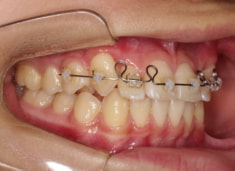

治療開始時